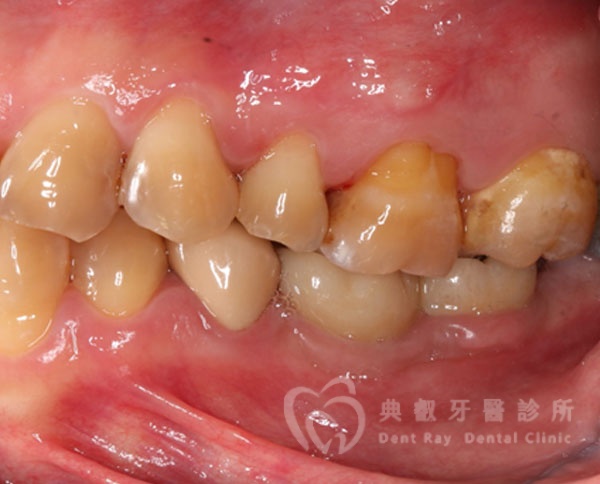

植牙案例三